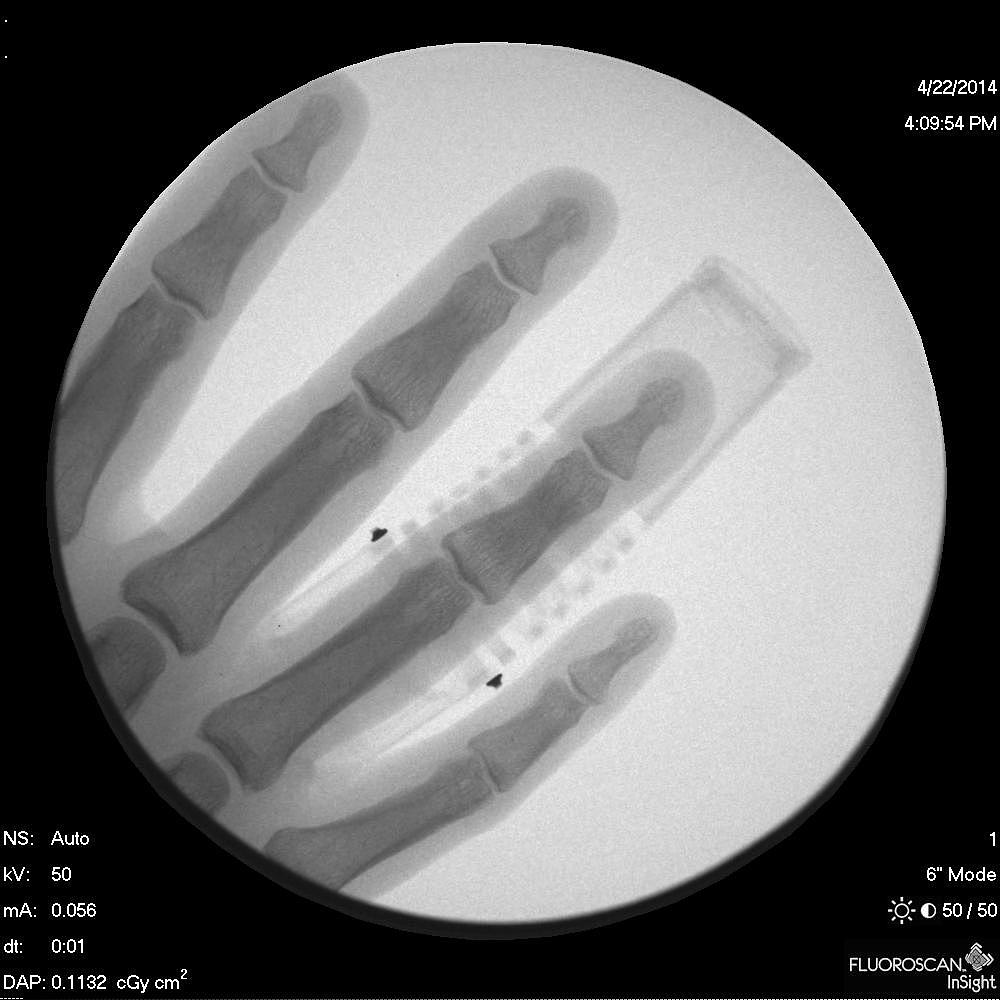

bend, a revolutionary medical finger split